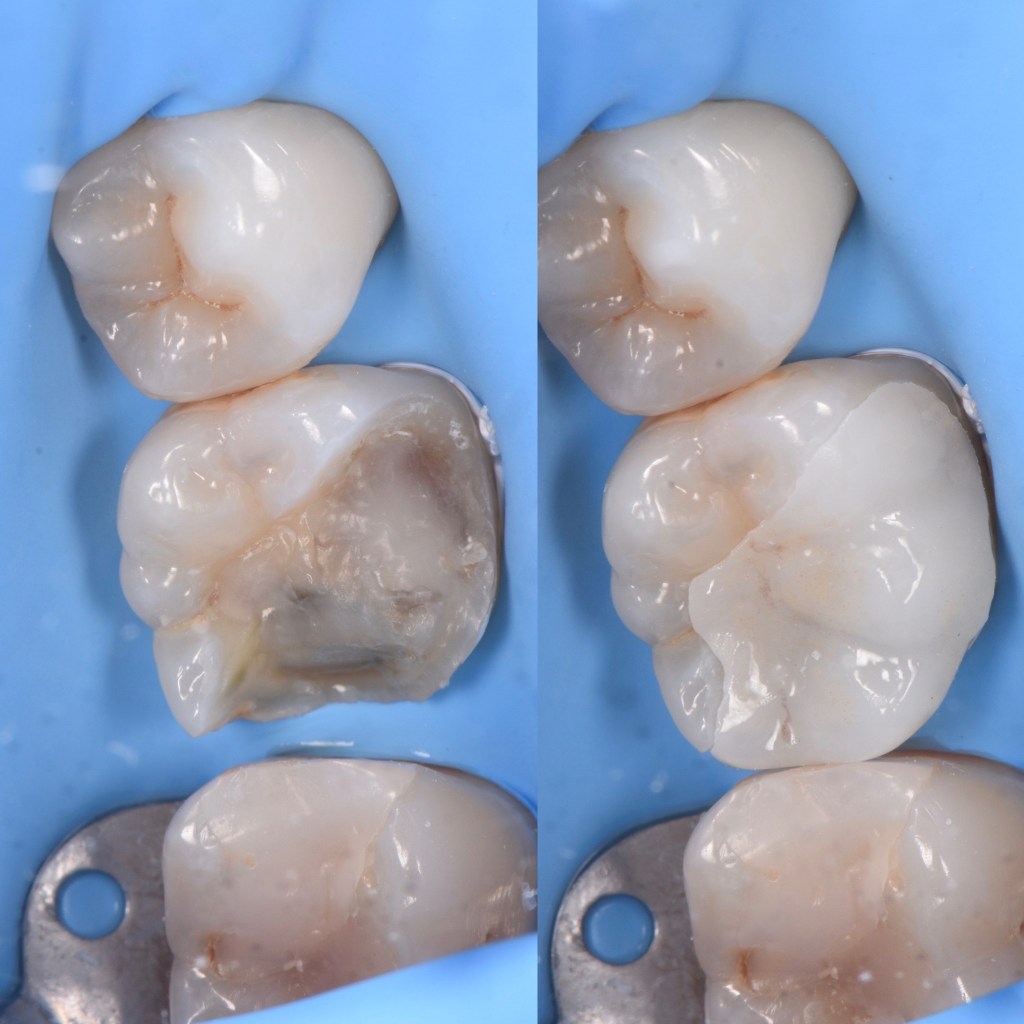

Réalisation de deux pièces en vitrocéramiques renforcées au disilicathe de lithium « onlays », réalisés au sein de notre laboratoire. La patiente présentait deux plombages cassés sur ses dents. Après les avoir enlevés, une empreinte a été réalisée, et seulement 1h après, les pièces ont été collées sous champ opératoire.

Ces deux photos illustrent parfaitement le concept d’onlay : c’est donc une petite pièce en céramique sur mesure qui vient restaurer la cavité causée par une précédente carie. Cela évite de préparer complètement la dent pour une couronne.